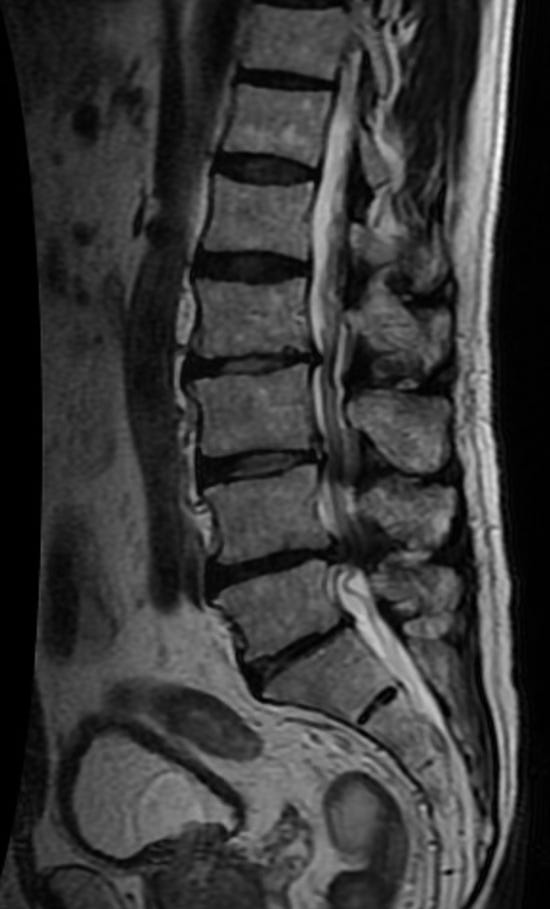

A proper diagnosis is based on symptoms, examination findings, and imaging, not imaging alone. MRI is generally considered the preferred imaging study because it provides a detailed view of the spinal canal, nerve spaces, discs, ligaments, and surrounding tissues (Katz et al., 2022; Webb et al., 2024). CT may be used when MRI is not appropriate.

Clinically, providers often look for the combination of leg-dominant symptoms, worse with walking or standing, improved with flexion or sitting, and a scan showing narrowing that makes sense with the patient’s presentation. On examination, a clinician may assess walking tolerance, balance, lumbar extension tolerance, neurologic function, lower-extremity strength, reflexes, sensation, hip mobility, and possible competing diagnoses such as vascular claudication, hip osteoarthritis, sacroiliac pain, or peripheral neuropathy (Webb et al., 2024).